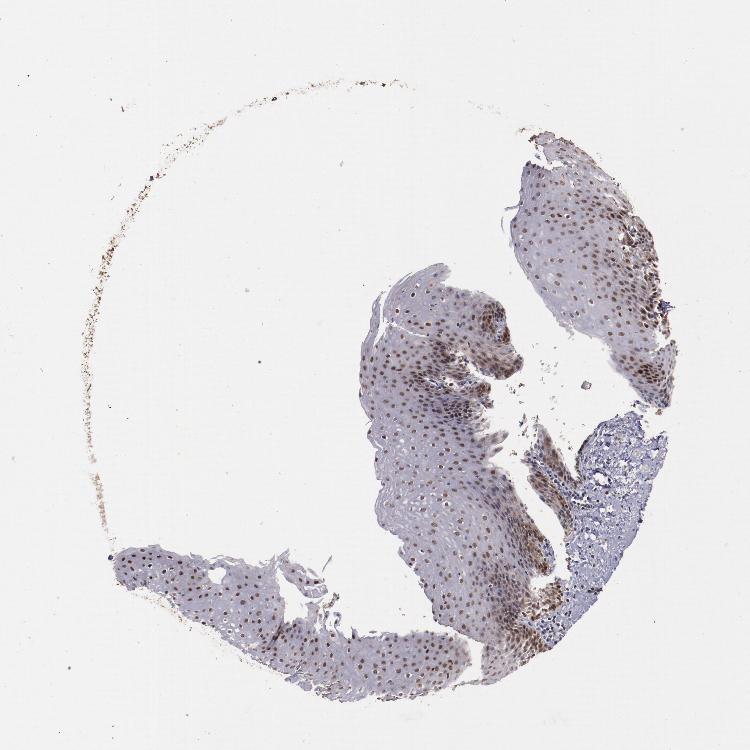

ESOPHAGUS - Antibody stainingi

Antibody staining in the annotated cell types in the current human tissue is reported as not detected, low, medium, or high, based on conventional immunohistochemistry profiling in selected tissues. This score is based on the combination of the staining intensity and fraction of stained cells.

Each image is clickable and will lead to virtual microscopy that enables deeper exploration of all samples and also displays staining intensity scores, fraction scores and subcellular localization as well as patient and tissue information for each sample.

Antibody HPA001878Antibody CAB002030

Squamous epithelial cells HighNot detected